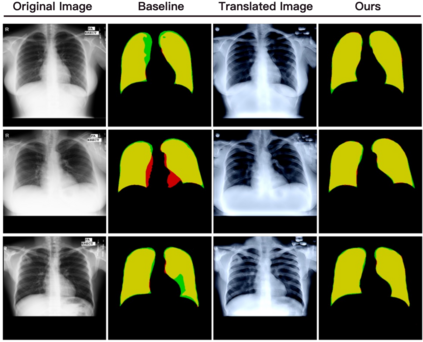

Deep-learning models have been successful in biomedical image segmentation. To generalize for real-world deployment, test-time augmentation (TTA) methods are often used to transform the test image into different versions that are hopefully closer to the training domain. Unfortunately, due to the vast diversity of instance scale and image styles, many augmented test images produce undesirable results, thus lowering the overall performance. This work proposes a new TTA framework, S$^3$-TTA, which selects the suitable image scale and style for each test image based on a transformation consistency metric. In addition, S$^3$-TTA constructs an end-to-end augmentation-segmentation joint-training pipeline to ensure a task-oriented augmentation. On public benchmarks for cell and lung segmentation, S$^3$-TTA demonstrates improvements over the prior art by 3.4% and 1.3%, respectively, by simply augmenting the input data in testing phase.